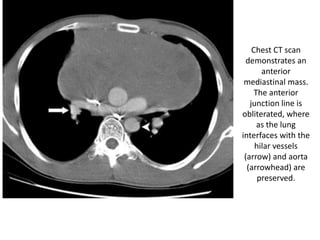

Chest

radiograph

shows the AP

window with

an abnormal

convex border

(arrow)

CT scan demonstrates lymphadenopathy (arrow), which accounts for

the distortion of the AP window

Chest radiograph shows the AP windowwith an abnormal convex border (arrow)

CT scan demonstrateslymphadenopathy (arrow), which accounts for the distortion of the AP window